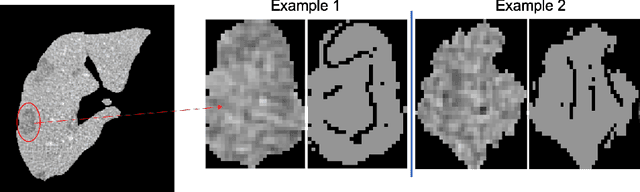

Abstract:Lesion synthesis received much attention with the rise of efficient generative models for augmenting training data, drawing lesion evolution scenarios, or aiding expert training. The quality and diversity of synthesized data are highly dependent on the annotated data used to train the models, which not rarely struggle to derive very different yet realistic samples from the training ones. That adds an inherent bias to lesion segmentation algorithms and limits synthesizing lesion evolution scenarios efficiently. This paper presents a method for decoupling shape and density for liver lesion synthesis, creating a framework that allows straight-forwardly driving the synthesis. We offer qualitative results that show the synthesis control by modifying shape and density individually, and quantitative results that demonstrate that embedding the density information in the generator model helps to increase lesion segmentation performance compared to using the shape solely.

Abstract:The success of supervised lesion segmentation algorithms using Computed Tomography (CT) exams depends significantly on the quantity and variability of samples available for training. While annotating such data constitutes a challenge itself, the variability of lesions in the dataset also depends on the prevalence of different types of lesions. This phenomenon adds an inherent bias to lesion segmentation algorithms that can be diminished, among different possibilities, using aggressive data augmentation methods. In this paper, we present a method for implanting realistic lesions in CT slices to provide a rich and controllable set of training samples and ultimately improving semantic segmentation network performances for delineating lesions in CT exams. Our results show that implanting synthetic lesions not only improves (up to around 12\%) the segmentation performance considering different architectures but also that this improvement is consistent among different image synthesis networks. We conclude that increasing the variability of lesions synthetically in terms of size, density, shape, and position seems to improve the performance of segmentation models for liver lesion segmentation in CT slices.